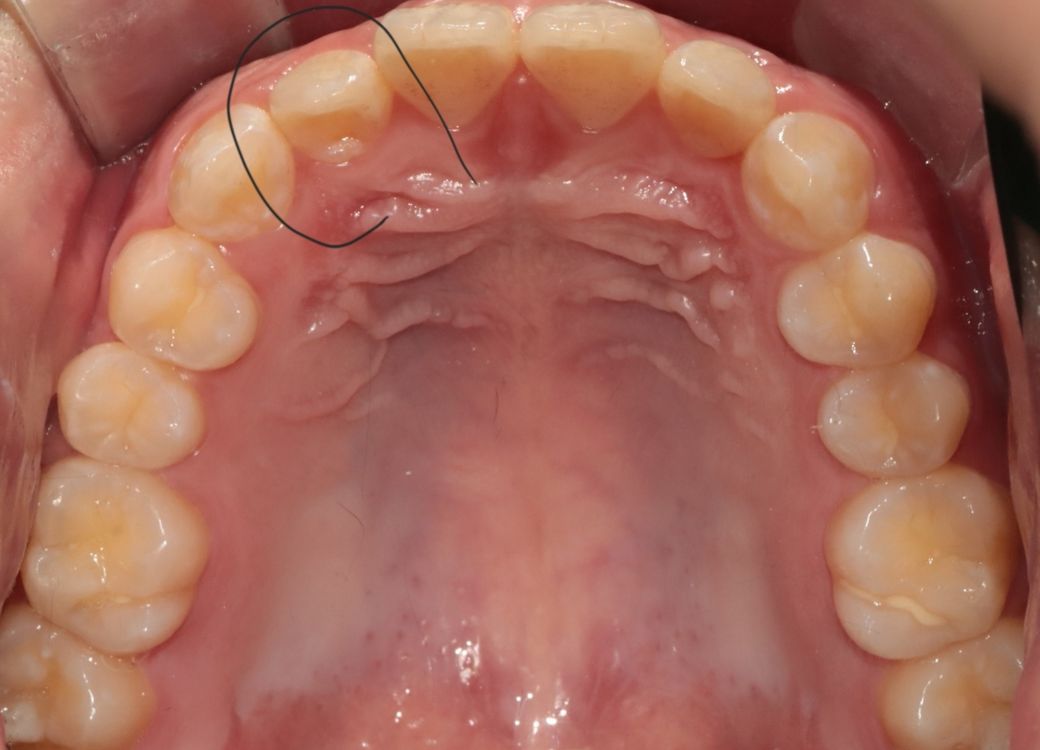

교정전부터 뼈 비대칭 때문에 치아중심선이 조금 안맞은 상태였는데 두번째앞니 전방으로 빼고있는 상태인데 두번째 앞니를 앞으로 빼다보면 교정완료후에 치아중심선이 더 안맞아보이거나 틀어질수도 있나요?

• 3번 째 사진